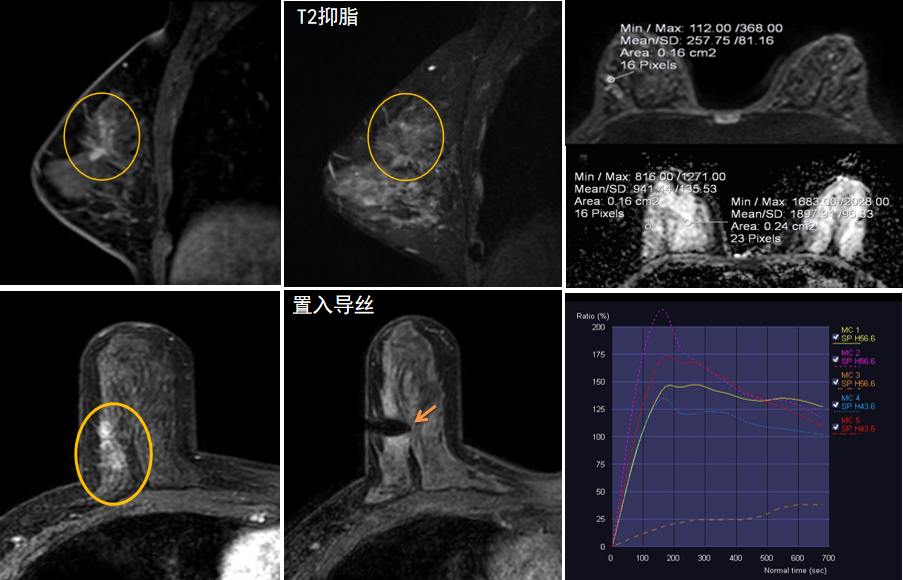

今年45歲的某女士,兩個(gè)月前行超聲檢查發(fā)現(xiàn)右乳結(jié)節(jié),乳腺X線攝影檢查提示右乳外上象限局部腺體結(jié)構(gòu)扭曲并簇狀無(wú)定形鈣化,為了進(jìn)一步評(píng)估病變性質(zhì)并確定范圍進(jìn)行了乳腺M(fèi)R平掃 DWI 增強(qiáng)的檢查,經(jīng)MR評(píng)估發(fā)現(xiàn)右乳病變范圍較廣,評(píng)估為BI-RADS 4類可疑病變,需要取得病理學(xué)結(jié)果。

西安國(guó)際醫(yī)學(xué)中心醫(yī)院影像診療中心陳寶瑩主任團(tuán)隊(duì)有著十余年影像引導(dǎo)下乳腺介入診療的經(jīng)驗(yàn),借助醫(yī)院高精尖的MR平臺(tái),成為西北首個(gè)全面展開(kāi)MR引導(dǎo)下各項(xiàng)乳腺介入診療技術(shù)的團(tuán)隊(duì),能夠?qū)Τ暭叭橄賆線無(wú)法顯示或顯示不清的病變進(jìn)行MR引導(dǎo)下的導(dǎo)絲定位、穿刺活檢及真空輔助旋切。

陳寶瑩主任及其帶領(lǐng)的MR介入診療小組詳細(xì)詢問(wèn)了病情,分析了患者資料,并與患者和臨床醫(yī)生進(jìn)行了充分溝通,確定于手術(shù)前為患者實(shí)施MR引導(dǎo)下的病變穿刺導(dǎo)絲定位和體表范圍確定。手術(shù)前陳寶瑩主任帶領(lǐng)聶品醫(yī)師、馬小偉技師、韓愛(ài)萍護(hù)士長(zhǎng)等MR介入診療小組成員,借助MR高清的圖像顯示和定位系統(tǒng),確定病變范圍,精準(zhǔn)穿刺置入定位導(dǎo)絲,并準(zhǔn)確標(biāo)記出病變體表范圍,整個(gè)過(guò)程患者無(wú)任何不適。在定位導(dǎo)絲和體表范圍標(biāo)記的輔助下,甲乳外科劉曉敏主任精準(zhǔn)切除了病變,解除了患者的后顧之憂。

國(guó)內(nèi)外指南均建議40歲以上的女性每年行一次雙乳X線攝影(鉬靶)檢查,以篩查乳腺癌。對(duì)于乳腺癌高危人群40歲以前即建議開(kāi)始乳腺癌篩查,除了進(jìn)行乳腺X線攝影(鉬靶)篩查外需要補(bǔ)充MR檢查,MR檢查敏感性最高,能夠發(fā)現(xiàn)大量X線攝影和超聲檢查陰性的可疑病變,基于多模態(tài)、多參數(shù)的結(jié)構(gòu)和功能成像的基礎(chǔ)上,MR能夠精準(zhǔn)顯示病變位置、范圍以及病變內(nèi)的活性區(qū)域,MR引導(dǎo)下的介入診療不但解決了僅在MR顯示的病變的處置難題,而且能夠精準(zhǔn)定位活性區(qū)域,保證了定位、活檢及旋切的準(zhǔn)確性。